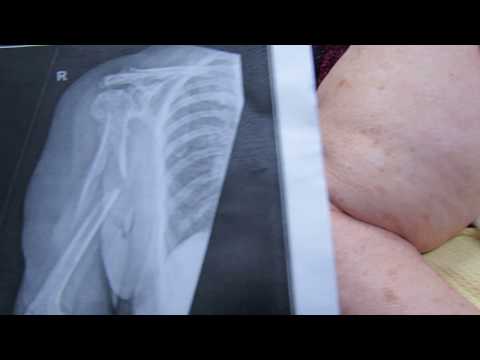

HUGE mid humeral fracture

Mystery Shoulder Injury course, in this course we will explore the diagnostic challenges associated with unidentified shoulder injuries. Participants will delve into the complexities of shoulder anatomy, common causes of shoulder pain, and diagnostic techniques such as clinical examination and imaging modalities. Through case studies and interactive sessions, learners will develop skills in differential diagnosis and problem-solving to accurately identify and manage mysterious shoulder injuries. This course aims to enhance understanding and proficiency in diagnosing and treating shoulder conditions with elusive etiologies, improving patient outcomes and quality of care.